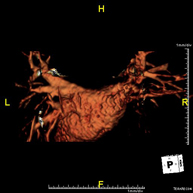

Prueba diagnóstica no invasiva que consiste en la obtención de imágenes de alta definición anatómica de las arterias cerebrales mediante el empleo de un campo electromagnético y ondas de radio (con un emisor y un receptor). No utiliza radiación ionizante. En la mayoría de los casos es necesario el empleo de contraste paramagnético (Gadolinio). Permite un estudio angiográfico no invasivo gracias a la inyección de Gadolinio con posterior reconstrucción en 2D y 3D, gracias a estaciones de trabajo especializadas. Indicaciones: malformaciones vasculares, aneurismas de arterias cerebrales, arteriosclerosis. - Angio-RM troncos supraaórticos

Prueba diagnóstica no invasiva que consiste en la obtención de imágenes de alta definición anatómica de las arterias carótidas y vertebrales a nivel de cuello, mediante el empleo de un campo electromagnético y ondas de radio (con un emisor y un receptor). No utiliza radiación ionizante. En la mayoría de los casos es necesario el empleo de contraste paramagnético (Gadolinio). Permite un estudio angiográfico no invasivo gracias a la inyección de Gadolinio con posterior reconstrucción en 2D y 3D, gracias a estaciones de trabajo especializadas. Indicaciones: problemas circulatorios cerebrales, síncope. - RM Espectroscopia Cerebral